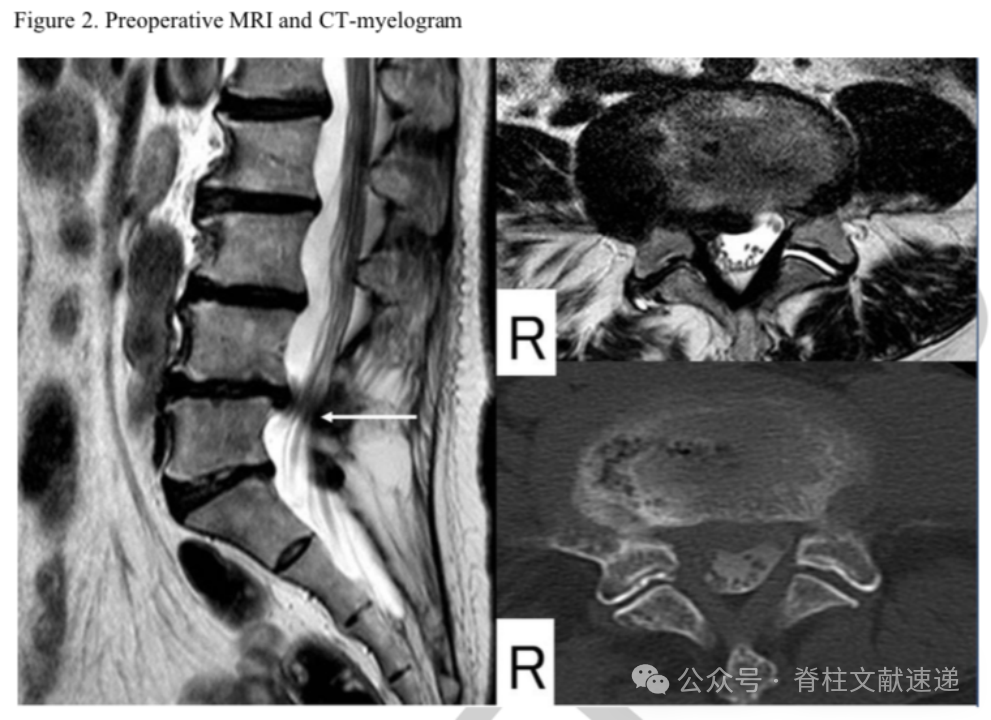

文中病例:69岁女性,右下肢放射性疼痛。存在脊柱侧弯,髓核摘除术后2月进行了融合手术。